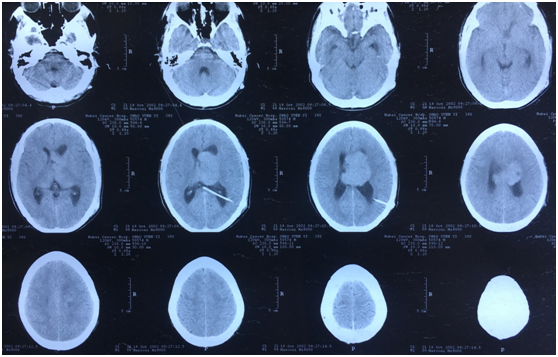

病例四脑室室管膜瘤1例mr影像表现

图片尺寸496x475